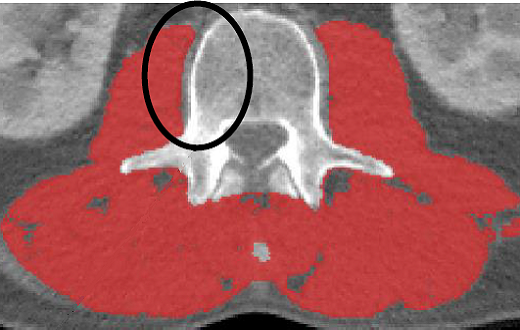

·The area underneath the vertebrae should remain untagged

·If the neural spine is present in the L3, the area underneath the neural spine should remain untagged